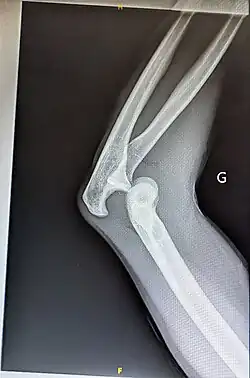

- Elbow

Prognosis varies depending on the location and extent of the dislocation. The prognosis of a shoulder dislocation is dependent on various factors including age, strength, connective tissue health and severity of the injury causing the dislocation.[23] There is a good prognosis in simple elbow dislocations in younger people. Older people report more pain and stiffness on average.[23] Wrist dislocations are often difficult to manage due to the difficulty in healing the small bones in the wrist.[23] Finger displacement towards the back of the hand is often irreducible due to associated injuries, while finger displacement towards the palm of the hand is more readily reducible.[23] Overall, recovering from a joint dislocation can range from a few weeks to months, depending on the severity of the injury.[4]